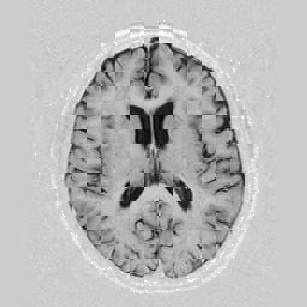

I later attempted 10 iterations at level 2, then 2 iterations at level 1, and 1 iteration at the finest level. Visual results can be seen in Figure [*].

Figure: Multi-scale NRR. From left to right, top then bottom: before NRR; after 10 iterations of NRR at level 2; after another 2 iterations of NRR at level 1; after 1 iteration at level 0.